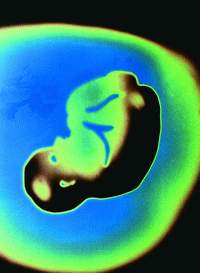

在最后的几周内,胎儿可以使用他的各个感官了。视觉在子宫里是最用不着的东西了,但是光线透过妈妈的赤裸的肚皮时,睁着眼的胎儿会把脸转向光亮的方向。他只能看见一种模糊的光亮,仿佛我们用手捂住手电筒时看到的光一样。

过去几个月里,他一直觉得自己这个小小的“家”紧紧包着他,仿佛妈妈在搂抱着他似的。今天,好像妈妈越来越紧地搂着她,而且越抱越紧。有节律的按压持续着,头部的压力不断加强。突然,头部的压力解除了——他的头部分娩出来了。然后,身体的其余部分也从妈妈的体内出来了。光亮、寒冷,一下子失去的束缚弄得他很不舒服,他于是哭了起来,踢着小腿,紧闭着双眼。

分娩时,宫缩的压力会阻止血液流经胎盘,从而造成了一阵阵的缺氧,但对于一个发育良好的健康婴儿是没有问题的。